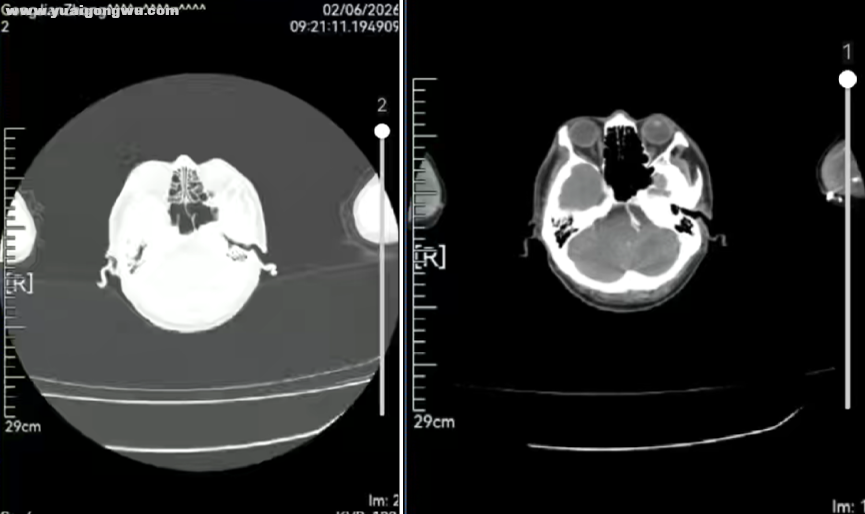

6 R* y; C# j }) a7 g* X1 r; K2026-1-12头部增强MRI:双侧小脑及大脑软脑膜多发增厚强化;左侧小脑半球及左侧颞叶强化结节:考虑脑转移。右侧半卵圆中心病灶并弥散受限,考虑脑转移瘤可能性大,脑萎缩。

- y0 M4 }4 P3 M3 s$ W2 _" A张旭教授(放疗科) 脑转移合并脑膜转移的治疗难度较大,结合头部核磁可见颅内多发转移灶及脑膜强化,结合脑脊液病理结果,该诊断可明确。理论上,脑膜转移伴脑脊液阳性者需行全脑全脊髓放疗,但临床实践中,该方案患者耐受度极低,且放疗剂量难以达标。该患者仅行全脑放疗即出现明显恶心、呕吐等不良反应,目前全脑放疗已是此类患者(脑转移、脑膜转移或脑脊液病理阳性)的常用且公认的治疗方式。全脑放疗期间需监测患者颅内压,若出现高颅压症状,需使用甘露醇脱水以缓解恶心、呕吐等不适。 0 x! }8 T0 V. B' b2 B/ N% _- y